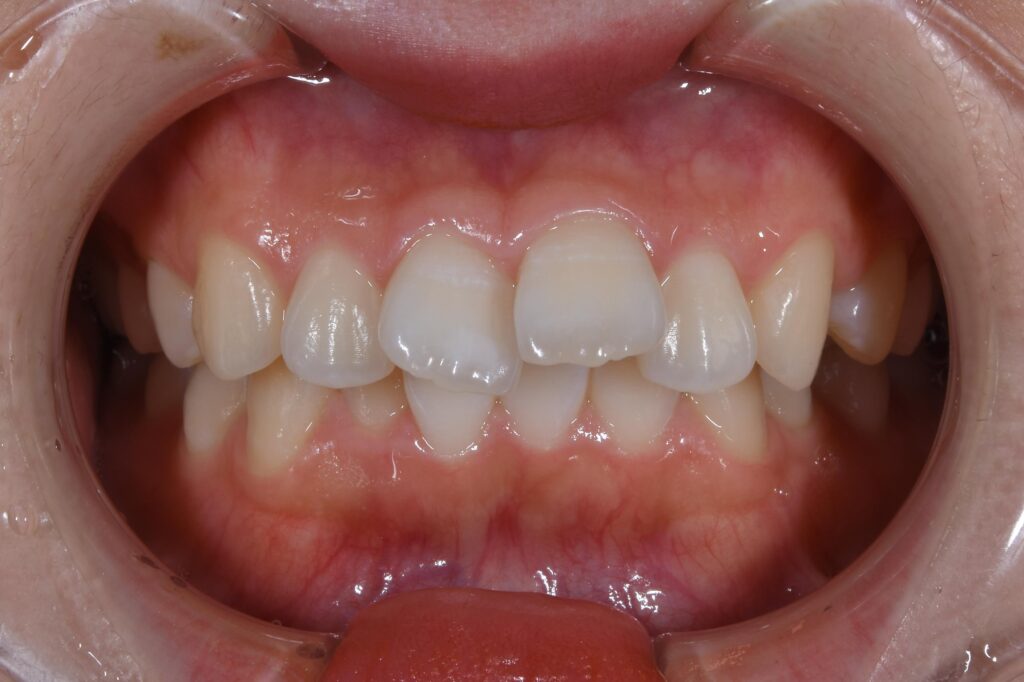

まずは初診時の状態です。

【初診時】

全体的に上の前歯が突出しています。